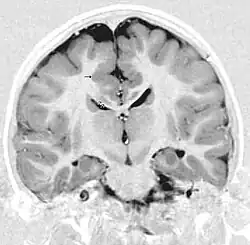

Diagnostik

Das Bildgebendes Verfahren der Wahl ist die Kernspintomographie.[6][10][9] Das heterotope Gewebe entspricht in seiner Signalgebung in allen Sequenzen der von grauer Substanz. In der fMRT kann mit BOLD-Kontrast eine Aktivierung der Heterotopien gezeigt werden.[11]